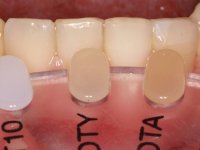

O paciente foi observado conjuntamente e a dúvida que surgiu de imediato foi se seria possível com a regeneração óssea a efectuar poder ser reabilitada naturalmente a zona das papilas interdentárias. Nesse sentido foi feito um enceramento de diagnóstico que contemplaria as duas hipóteses, utilizando ou não a cerâmica gengival. A confecção desse enceramento foi fundamental para expor ao paciente a dificuldade da reabilitação. O wax-up deu origem a um mock-up que foi aprovado pelo paciente e que simultaneamente serviu de guia imagiológica. O caso foi planificado cirurgicamente e realizada uma guia cirúrgica com que foram colocados os implantes. Após 10 semanas foi feita a 1ª impressão para confecção da ponte provisória. Foram criados os primeiros perfis de emergência na gengiva artificial e foi digitalizado o modelo. Por processo de CAD-CAM foi confeccionada uma ponte provisória aparafusada baseada no enceramento de diagnóstico. A ponte trabalhou durante 8 semanas os tecidos moles que foram fielmente copiados numa impressão com técnica de moldeira aberta. Os transferes foram individualizados com resina composta para copiarem fielmente os perfis de emergência criados pela ponte provisória. Confeccionado o modelo de trabalho definitivo, foi realizada uma infra-estrutura em zircónio seguindo a orientação do enceramento de diagnóstico. O assentamento da infra-estrutura foi testado em boca e simultaneamente foi novamente impressionados os tecidos moles com um silicone fluido. Nessa consulta foi feito o levantamento da cor. Os dentes 13 e 23 apresentavam uma saturação anormalmente forte que resolvemos não valorizar, optando por privilegiar a relação com o sector antero-inferior. Foi realizada uma nova gengiva artificial com a impressão que acompanhou a impressão de arrasto com a infra-estrutura. Após a colocação da cerâmica na infra-estrutura foram coladas as meso-estruturas. O trabalho final foi aparafusado lentamente permitindo a adaptação dos tecidos moles.